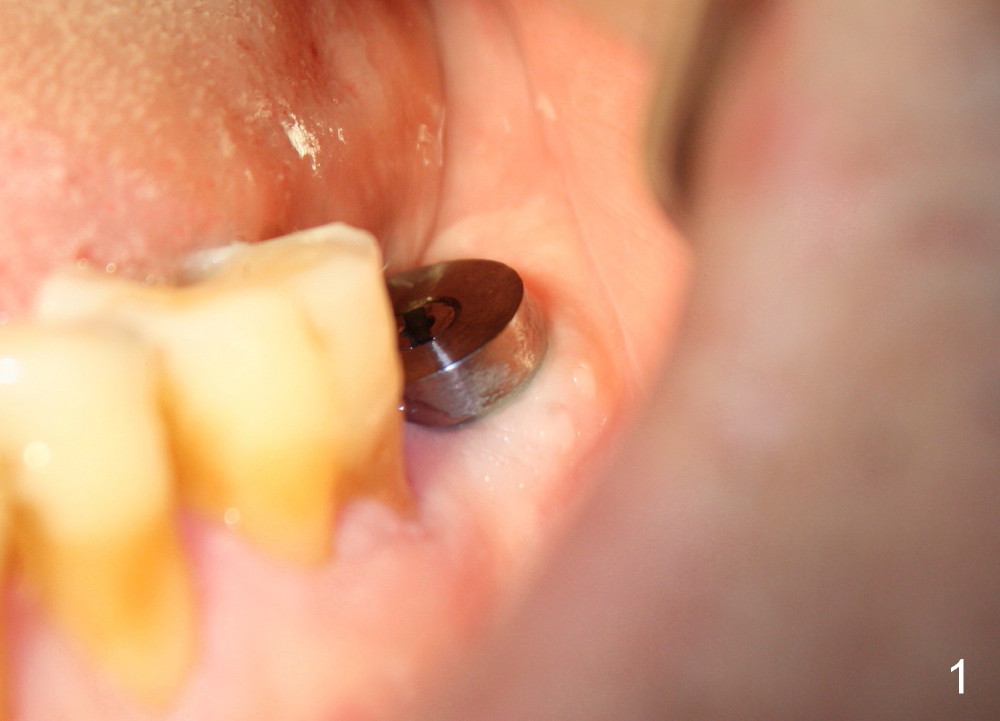

The soft tissue heals around the implant 1 months postop (Fig.1), but the implant (7x11 mm) is unstable. It should have been placed 2 mm deeper (Fig.2). It is splinted for the neighboring tooth (Fig.3). When the splint is removed 4 months later, the implant remains mobile. It is removed with infiltration anesthesia. The osteotomy is deepened by approximately 2 mm. A 7x14 mm tap is inserted with stability (Fig.4); there is apical space to be engaged further (arrowheads). A 7x14 mm implant is placed with insertion torque > 60 Ncm (Fig.5 I); an abutment (A) placed to keep perio dressing in place.

In contrast, the patient is asymptomatic after the 2nd placement. The implant remains stable (Fig.6 (15 days postop); Fig.7 (4 months postop)).